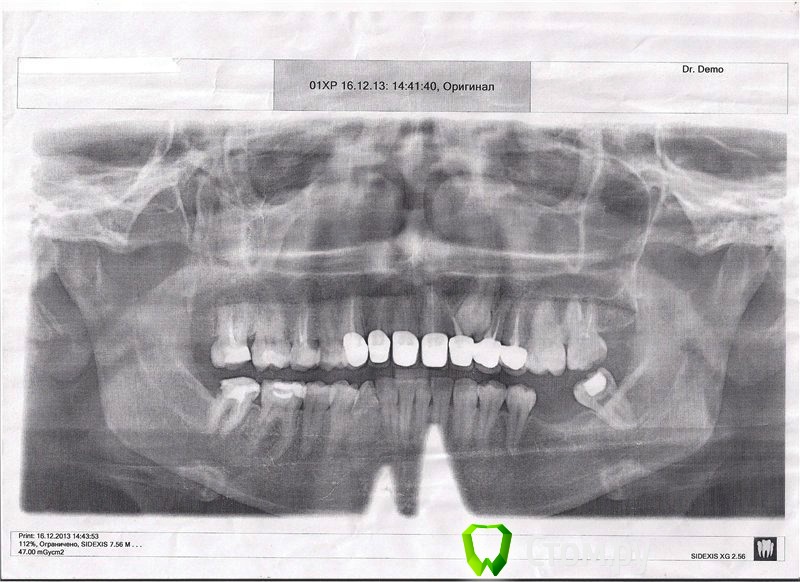

IvanK Опубликовано 17 декабря, 2013 Поделиться Опубликовано 17 декабря, 2013 Снимок плохого качества... он распечатан на бумаге? Попросите скинуть на флешку электронный вариант. 17, 15, 27, 47- перелечивать , с последующим протезированием коронкой.Консультация ортодонта,Протезирование с попрой на имплантаты 37,36, удаление 38 очень важно воссоздать контактные пункты между зубами. оценить коронки можно только при очной консультации у Врача Ортопеда.На снимке виден ретенированный клык.. Дискомфорт в области Ваших коронок может быть связан с плохим прилеганием коронок, клыком.. Ссылка на комментарий

red_butler Опубликовано 17 декабря, 2013 Поделиться Опубликовано 17 декабря, 2013 С поправкой на качество снимка - каких-либо серьезных пародонтальных проблем в области новых коронок я не вижу. Линкомицин больше не колите, Вас ведь не провязывают к креслу и насильно не колят. Когда увидем снимок надлежащего качества, можно будет судить о лечении корневых каналов. 1 Ссылка на комментарий